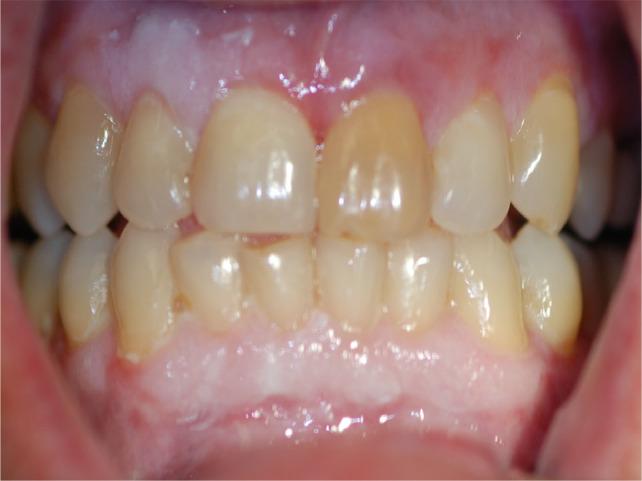

Graft-versus-host disease (GVHD) is a complication of haematopoietic stem cell transplantation (HSCT). GVHD may also develop following solid transplants or blood transfusions if white blood cells are transferred. GVHD affects multiple organs, including the oral tissues.

Acute GVHD may manifest in the oral mucosa; however, it often develops immediately following HSCT when routine dental treatment is postponed. Chronic GVHD may manifest in the oral mucosa, the salivary glands and the musculoskeletal compartment. It may indirectly affect the teeth and the oral flora, putting the patient at risk for infections. Importantly, GVHD poses an increased risk for oral cancer.

移植物抗宿主病(GVHD)是造血干细胞移植(HSCT)的一种并发症。如果白细胞被转移,GVHD 也可能在实体器官移植或输血后发生。GVHD 影响多个器官,包括口腔组织。

急性 GVHD 可能在口腔黏膜中表现出来;然而,它通常在 HSCT 后立即发生,此时常规的牙科治疗被推迟。慢性 GVHD 可能在口腔黏膜、唾液腺和肌肉骨骼部位表现出来。它可能会间接影响牙齿和口腔菌群,使患者面临感染的风险。重要的是,GVHD 增加了口腔癌的风险。